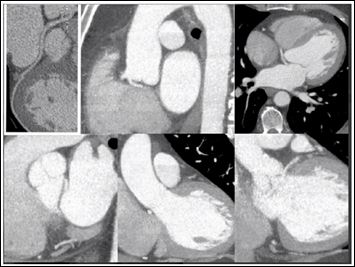

Cardiac catheterization was done given the patient’s high risk for Coronary Artery Disease (CAD) and chest pain complaints. The differential diagnosis would include occlusive coronary artery disease, Prinzmetal angina, microvascular coronary artery disease, coronary syndrome X, spontaneous coronary artery dissection, anomalous coronary artery with interarterial course. The coronary angiogram revealed an anatomic anomaly of the left main coronary artery (Figure 1). There was no obstructive CAD found. Coronary Computed Tomography Angiography (CTA) was subsequently ordered to further assess the anatomy and origin of the coronary arteries. CTA revealed a single coronary ostium with common origin of the right and left coronary arteries arising from the right sinus of Valsalva. The left coronary artery coursing posteriorly between the aortic root and left atrium, without an abrupt acute angle, intramural course, or fish-mouth ovoid appearance of the ostium (Figure 2).

Figure 2: Coronary CTA images in the coronal, transverse, and sagittal planes revealing anomalous left main coronary artery from the right cusp of the sinus of Valsalva sharing a common ostium with the right coronary artery. The left main coronary artery takes aposterior and inferior course between the left atrium and aortic root.